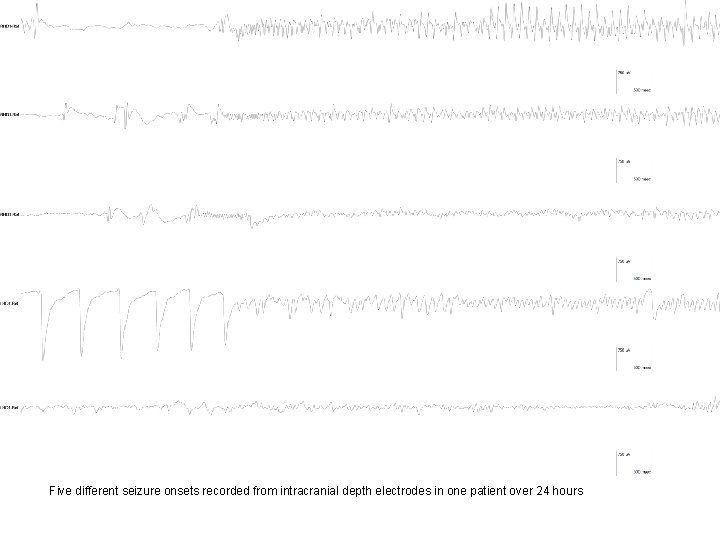

Five different seizure onsets recorded from intracranial depth electrodes in one patient over 24 hours

…Continuation of the five seizures from previous figure